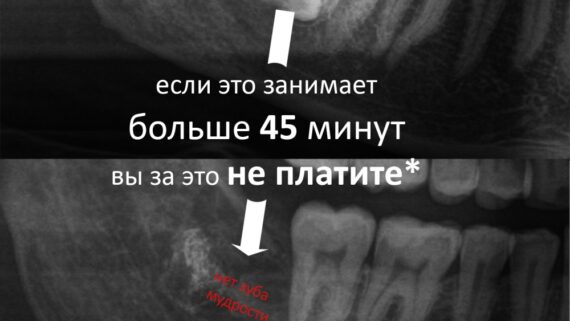

- Лечитесь вовремя. То есть, не нужно ждать, «пока заболит и опухнет». Любые болезни намного сложнее лечатся в острой стадии, а дискомфорт и риск осложнений вырастают до заоблачных вершин. Чем больше болезнь запущена — тем сложнее (и дороже) ее вылечить.

С той же остеопластикой — чаще всего ее проводят из-за выраженной атрофии костной ткани, которая вызвана длительным отсутствуем зубов. Если бы пациенту вовремя (в идеале — сразу) поставили импланты и провели протезирование — остеопластики удалось бы избежать. А, если вовремя заняться лечением зубов — возможно, был бы шанс избежать их удаления и последующей имплантации. - Не экономьте на квалификации и опыте врача. Ищите компетентного специалиста, применительно к Вашему случаю.